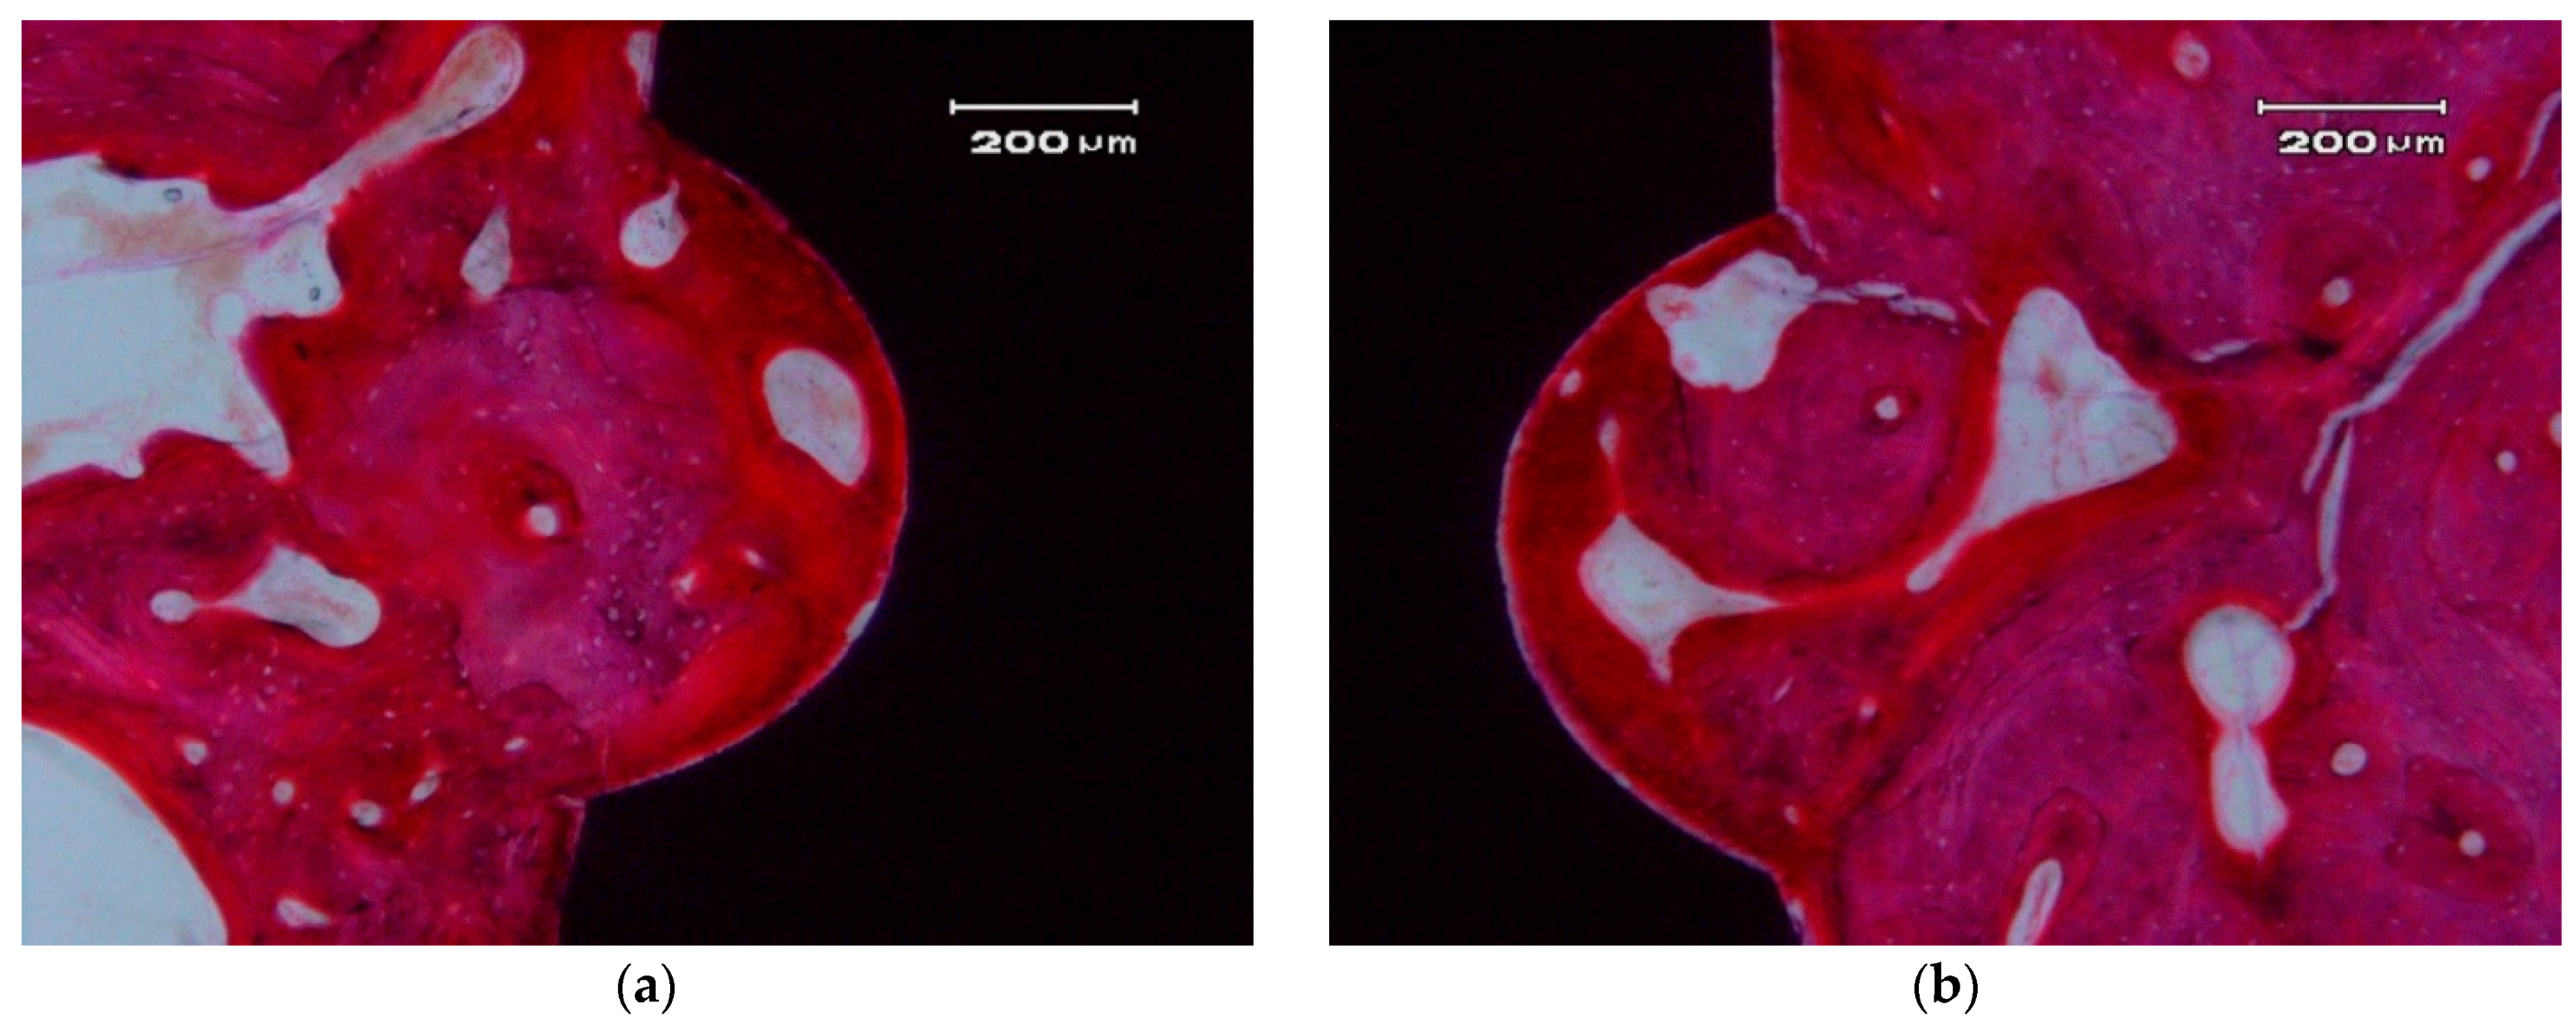

Figure 6.

Bone apposition on the surface of a ZCe-A implant after eight weeks of healing (longitudinal cross-section). The bone in contact with the implant shows a lamellar and Haversian structure. (a) left side and (b) right side of the implant

In the hard tissue area, a direct and close apposition of the bone matrix to the implant surface is observed, without the presence of a non-mineralized connective tissue interface.

The soft, gingival, peri-implant tissue is found to be in perfect contact with the implant. There is a close epithelial adhesion to the implant surface (Figure 7a) without lymphocytic infiltrate, disruption of the keratinized gingival structure, or alterations of the connective tissue attachment (Figure 7b). Secondary and tertiary osteons and vascular buds are seen nearby the implant’s surface (Figure 7a). Bone grows inside the thread’s valleys in intimate contact with the implant and very clear reversal lines can be observed delineating the different stages of bone remodeling (Figure 7b). There are no signs of inflammation or implant rejection by the bone, nor atypia or dysplasia.